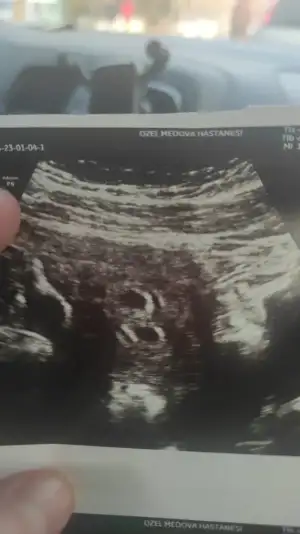

Bende size güzel haberi vereyim o halde sanırım bebeklerim ikiz 🤭🧿 tek yumurtam vardı maşallah barekallah umarım ikisi de benimle kalır ❤️ dualardan eksik etmeyin bizi teyzeleri

• IMG-20230104-WA0011.webp

IMG-20230104-WA0011.webp

18 KB · Görüntüleme: 49